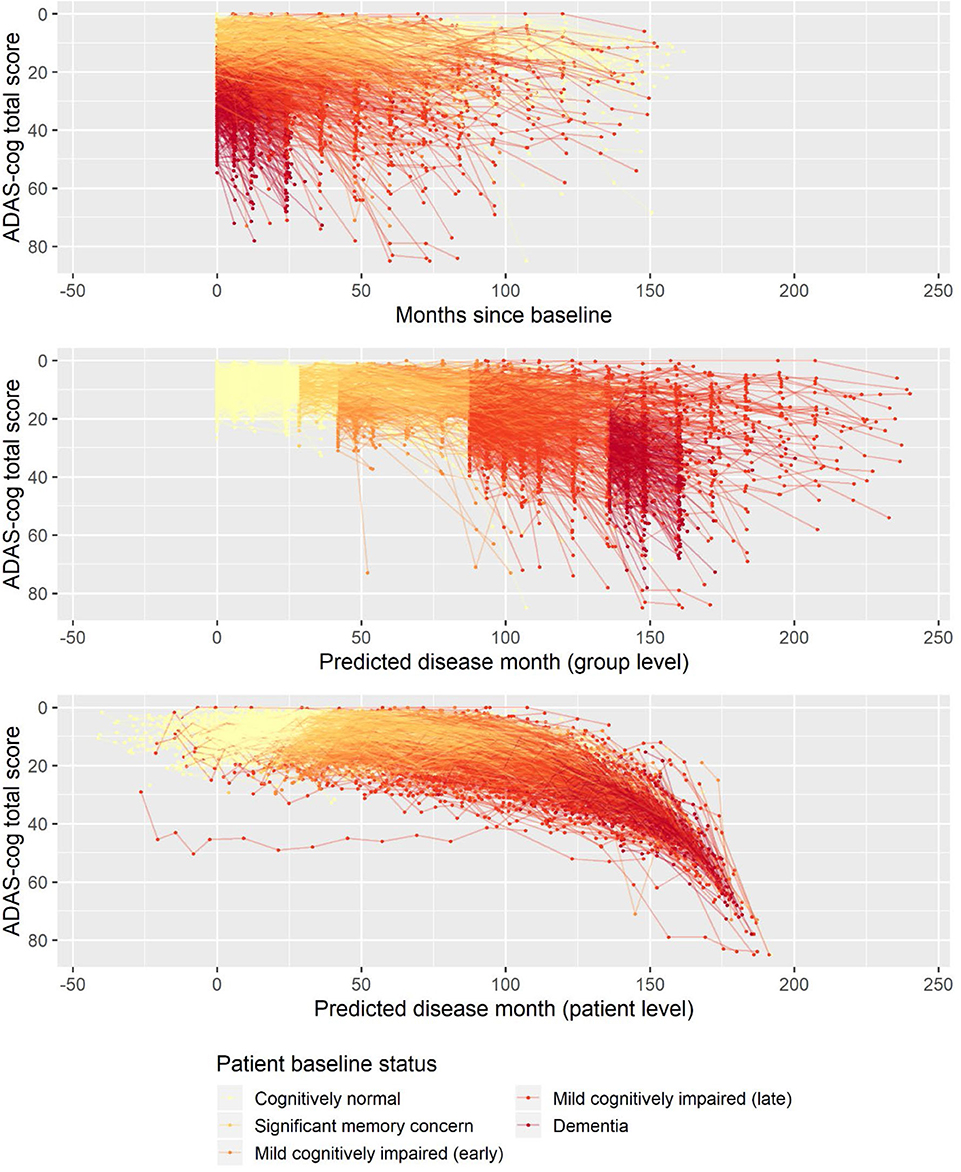

Embrace seasonal changes with our predicting alzheimers disease progression using a versatile sequence gallery of countless weather-themed images. highlighting time-sensitive blue, green, and yellow. perfect for seasonal marketing and campaigns. Each predicting alzheimers disease progression using a versatile sequence image is carefully selected for superior visual impact and professional quality. Suitable for various applications including web design, social media, personal projects, and digital content creation All predicting alzheimers disease progression using a versatile sequence images are available in high resolution with professional-grade quality, optimized for both digital and print applications, and include comprehensive metadata for easy organization and usage. Explore the versatility of our predicting alzheimers disease progression using a versatile sequence collection for various creative and professional projects. Advanced search capabilities make finding the perfect predicting alzheimers disease progression using a versatile sequence image effortless and efficient. Diverse style options within the predicting alzheimers disease progression using a versatile sequence collection suit various aesthetic preferences. Time-saving browsing features help users locate ideal predicting alzheimers disease progression using a versatile sequence images quickly. Regular updates keep the predicting alzheimers disease progression using a versatile sequence collection current with contemporary trends and styles. Reliable customer support ensures smooth experience throughout the predicting alzheimers disease progression using a versatile sequence selection process.